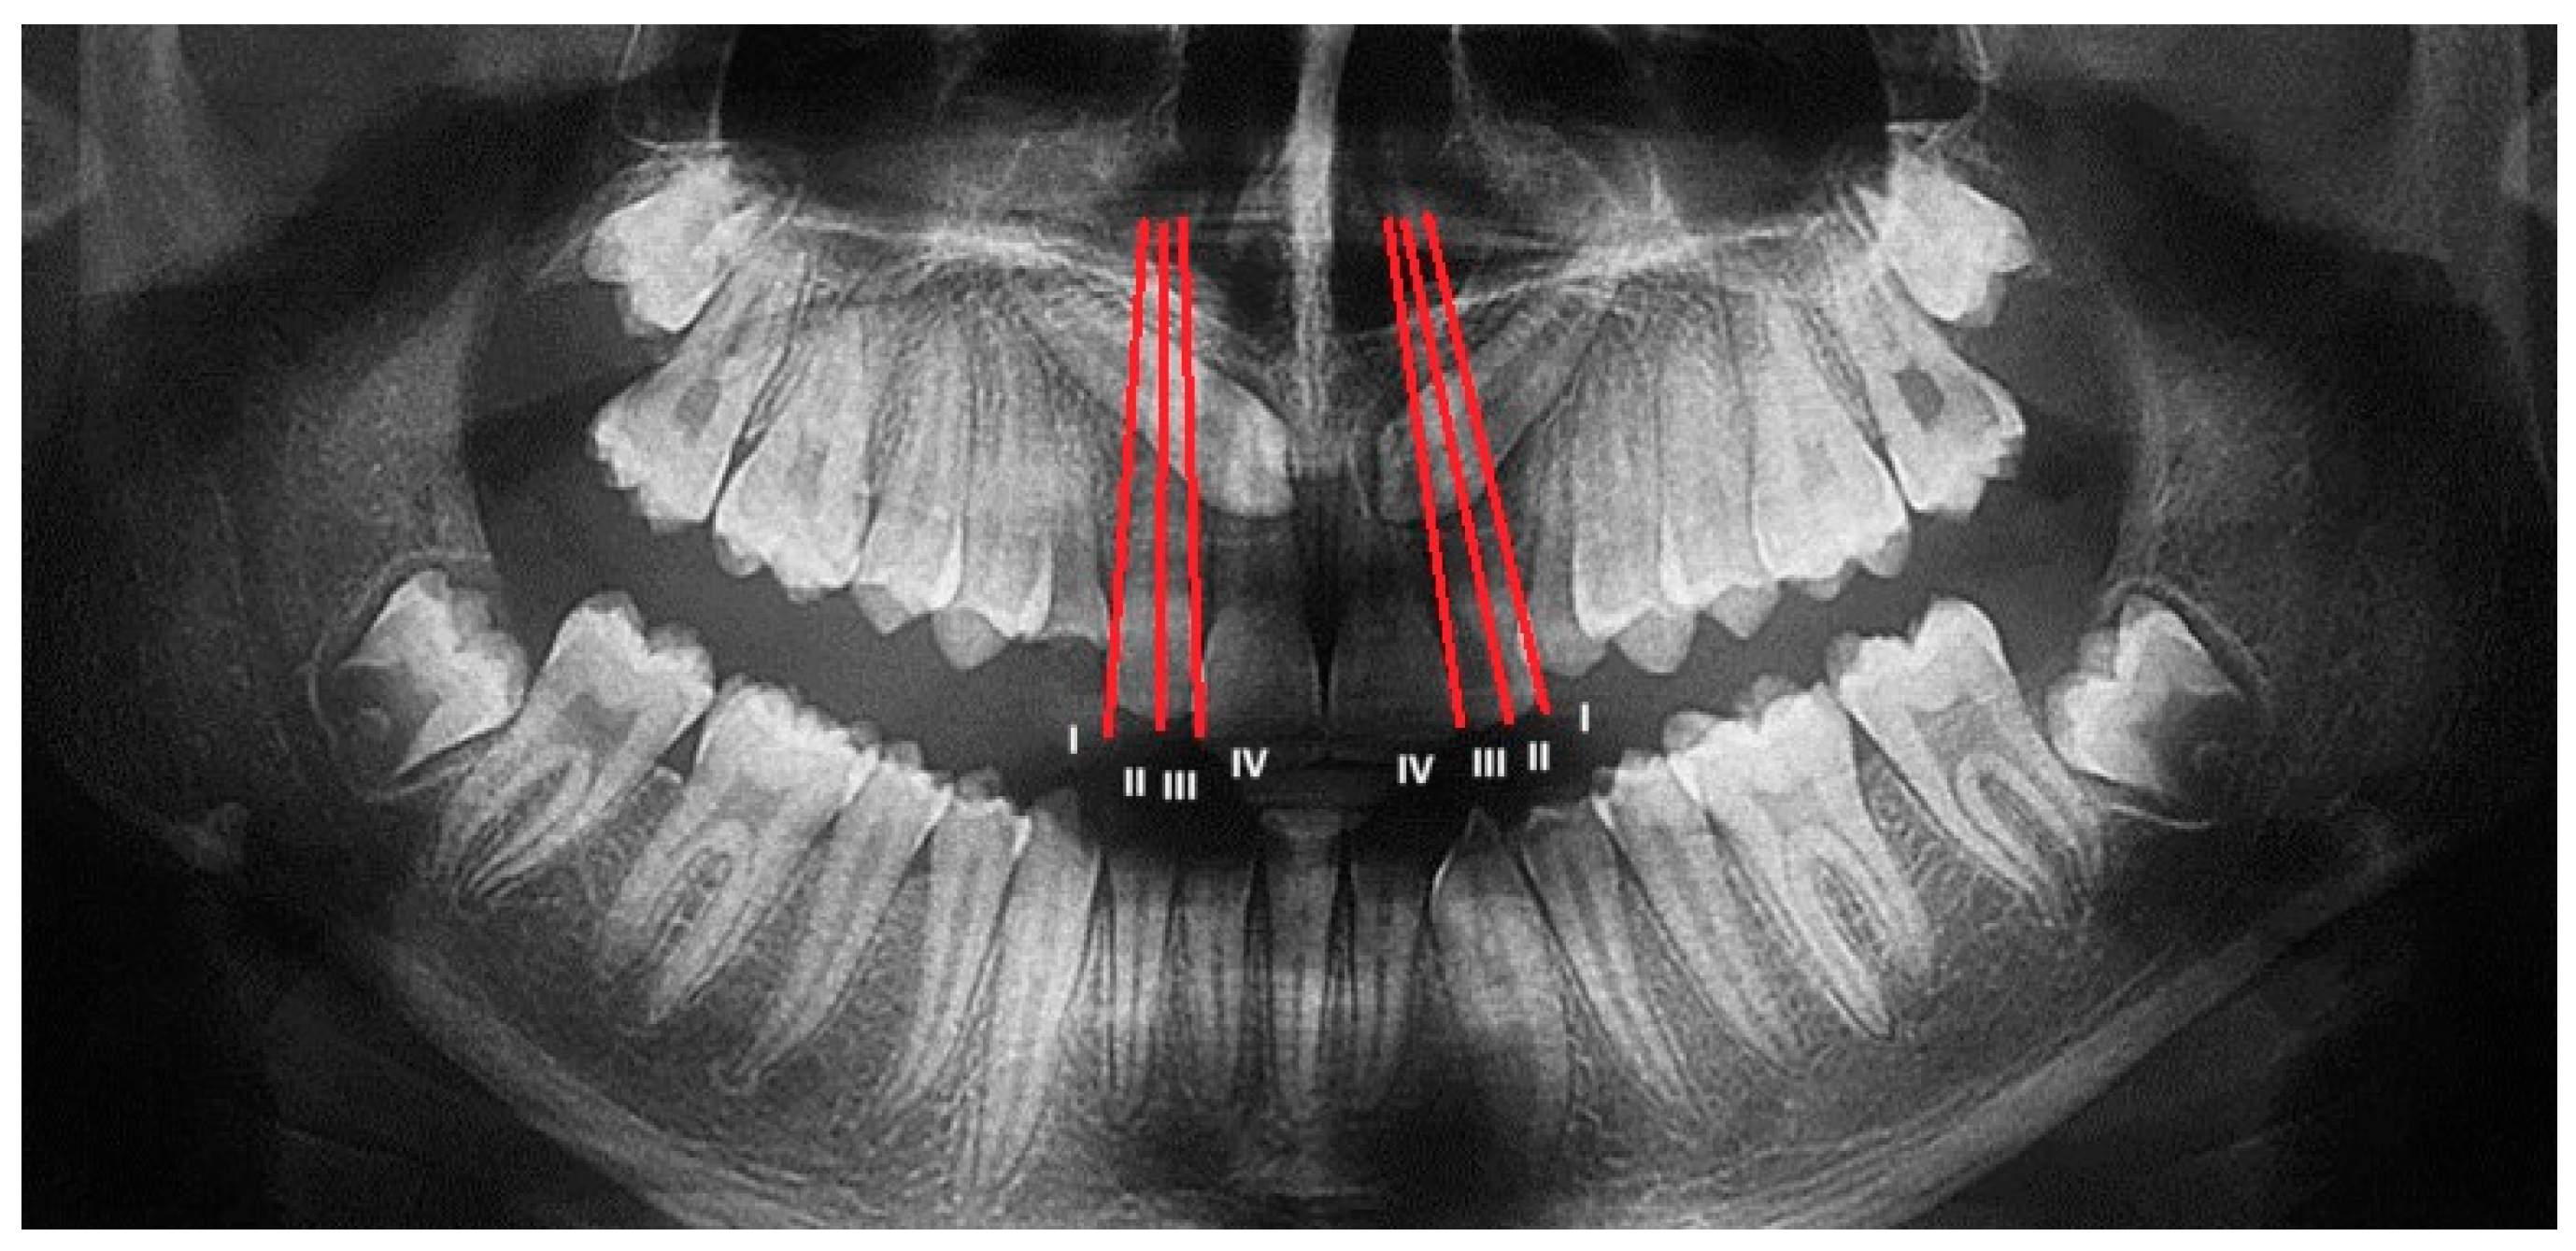

All patients underwent disinclusion surgery using a diode laser (Ka-Laser Blue Derma. Eltech K-Laser srl, Treviso, Italy) with wavelengths of 445 nm, 660 nm, and 970 nm. The laser was operated in continuous wave mode at a power output of 4 watts. The energy density (fluence) applied ranged from 0.5 to 8 J/cm2, tailored to tissue thickness and surgical requirements. Each application lasted between 15 and 30 s per treated site to ensure effective ablation and hemostasis while minimizing thermal damage. The focused laser beam allowed precise incision and coagulation, reducing operative trauma and promoting faster postoperative healing. All procedures were performed by the same operator, who performed an operculectomy using the high-intensity laser; if necessary, ostectomy was performed using a low-speed handpiece and under copious irrigation. At the end of the procedure, a periodontal pack (Coe-Pak, GC Dental, Tokyo, Japan, regular periodontal dressing, base 90 g + catalyst 90 g) was placed to protect the treated area of the palate, and it was removed after seven days. To assess the spontaneous eruption of canines, no orthodontic anchorage or traction was applied to all exposed canines (Figure 4).

Figure 4.

Diode laser disinclusion (diode laser K-Laser, Eltech, Blue Derma, 445–660–70 nm).